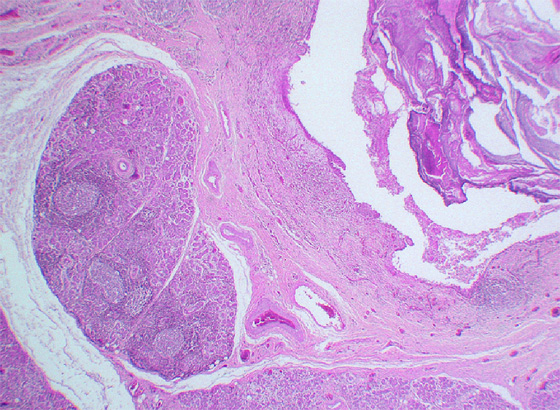

Microscopic finding (HE stain, low-power view). A sialolith (), with concentric laminations, is seen lodged inside a markedly dilated duct. There is pronounced chronic interstitial inflammation of salivary gland lobules () with lymphoid follicle formation (arrows). Intra and perilobular fibrosis are characteristic findings in chronic sclerosing sialadenitis. There is acinar atrophy and destruction with ductal dilatation (lower right).